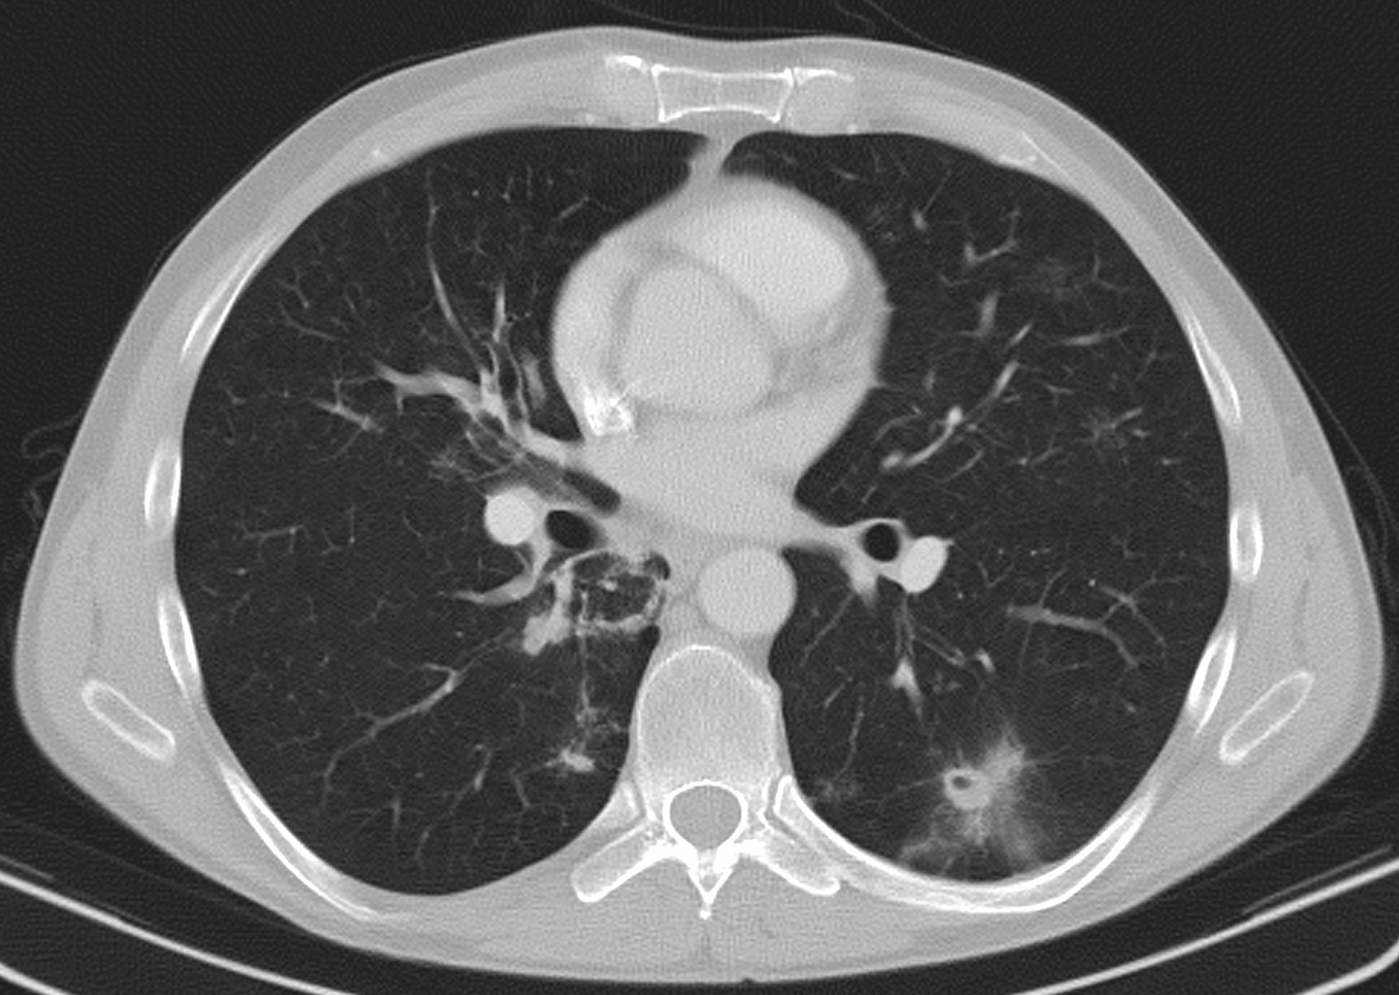

3a: Round shadow: multiple lung metastasis. Chest radiograph (PA)

3b: Multiple lung metastasis, CT lung window (axial, coronal reformat)

3c, coronal reformat

70 year old man, colon tumor.

Radiograph: Bilateral extensive, confluating patchy-nodular shadowing with diffuse reticular pattern. The diaphragm contour is partially blurry bilaterally: lymphangiosis carcinomatosa.

CT: Numerous 1-6 cm round and irregular, lobulated-spiculated contrast enhancing lesions in both lungs, everywhere sporadically.